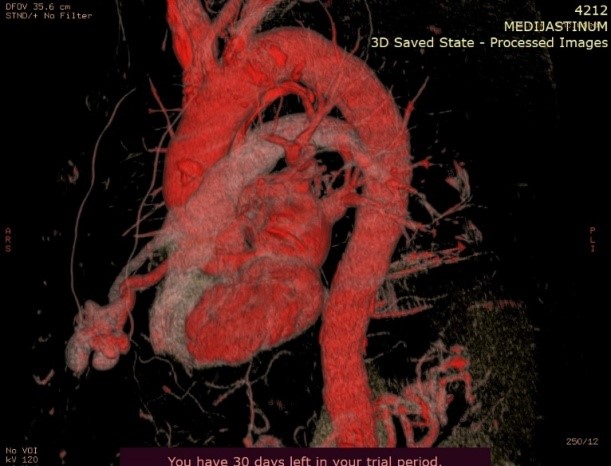

On the performed lung MDCT in the arterial phase, a fistula connecting arterial to venous vessels is clearly demarcated, with bridging of the normal capillary bed between them. The arterial blood vessel measures 3.47mm in diameter and may be a candidate for coil embolization.

Image 5. Maximum Intensity Projection (MIP) reconstruction of the AV fistula at the level of arterial and venous blood vessels in the right lung.

Image 6. Maximum Intensity Projection (MIP) reconstruction showing AV shunting into the pulmonary arteries.